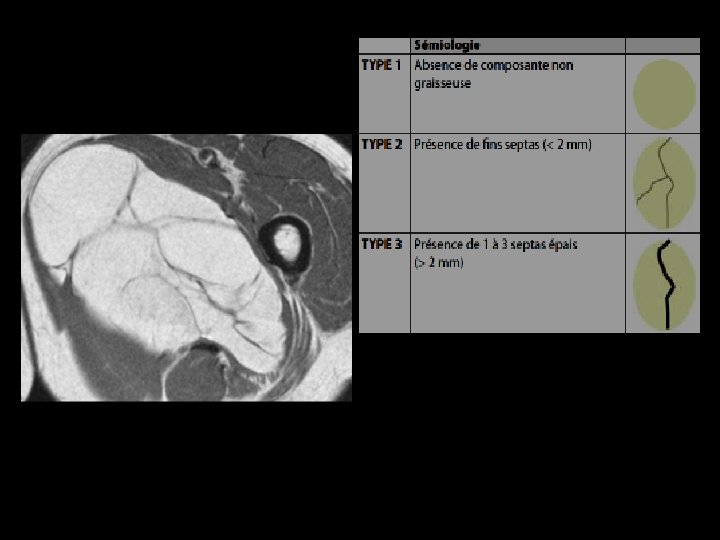

LIPOSARCOME BIEN DIFFERENCIE IRM: • Masse de signal graisseux - en hypersignal T 1 et T 2 - effacement du signal de la graisse • En faveur de la malignité: - septas épais > 2 mm - éléments nodulaires et tissulaires

Liposarcome bien différencié de la hanche Coupe axiale pondérée SE T 1 (a), frontale pondérée T 2 (b) et axiale pondérée SE T 1 avec Fat Sat et injection de Gadolinium (c): tumeur graisseuse avec des travées nombreuses et relativement épaisses

Critères IRM en faveur d’un sarcome • • Lésion de plus de 50 mm de diamètre Localisation sous aponévrotique Contours irréguliers ou lobulés Septa intra-tumoraux irréguliers et épais Hétérogénicité en T 1 et T 2 Présence de zones nécrotiques PDC précoce et prolongée

TUMEURS GRAISSEUSES BENIGNES LIPOME Localisation superficielle Taille < 5 cm Homogène Sépta < 2 mm Pas de nodules MALIGNES LIPOSARCOME BIEN DIFFERENCIE Localisation sous aponévrotique Taille >5 cm Hétérogène Sépta épais Éléments nodulaires et tissulaires